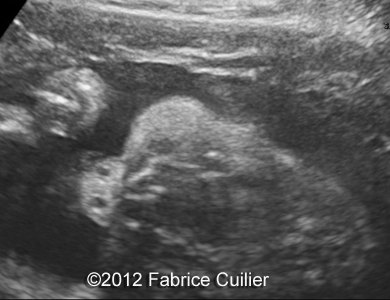

Image 6, 7 : 2D sagital views of the face at 29 weeks shows retrognatism with normal nose bones.

5

6